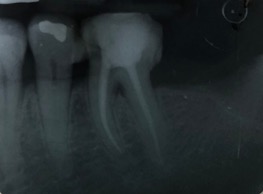

Una corretta terapia canalare con un perfetto sigillo a livello degli apici delle radici è fondamentale. I denti devitalizzati impropriamente possono creare ulteriori problemi che poi andranno a ripercuotersi sulle cure effettuate successivamente come le ricostruzioni e le corone protesiche con conseguente fallimento del piano terapeutico.

Capita spesso di incontrare denti già devitalizzati in maniera impropria che necessitano, seppur asintomatici, di essere ritrattati per evitare che i granulomi infetti visibili radiograficamente si evolvano riassorbendo tutto l’osso sottostante.